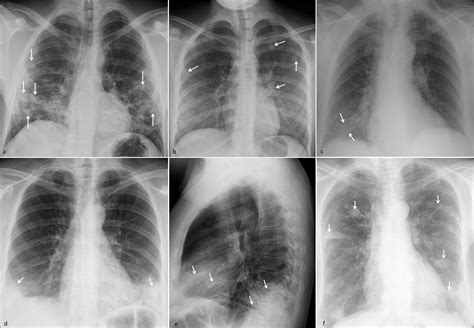

• Consolidation: This type of opacity appears as a homogeneous increase in lung density, often due to fluid or inflammatory cells filling the alveoli. It is commonly seen in conditions like pneumonia.

• Ground-glass opacity: This refers to an area of increased lung density that does not obscure the underlying bronchial structures. It can be caused by conditions such as interstitial lung disease or early stages of pneumonia.

• Nodules: These are small, round opacities that can be benign or malignant. They are often detected incidentally on imaging studies and require further evaluation.

• Masses: Larger opacities that are typically greater than 3 cm in diameter. They can be benign or malignant and require thorough investigation.

• Cavities: These are areas of necrosis within a mass or nodule, often seen in infections like tuberculosis or fungal infections.